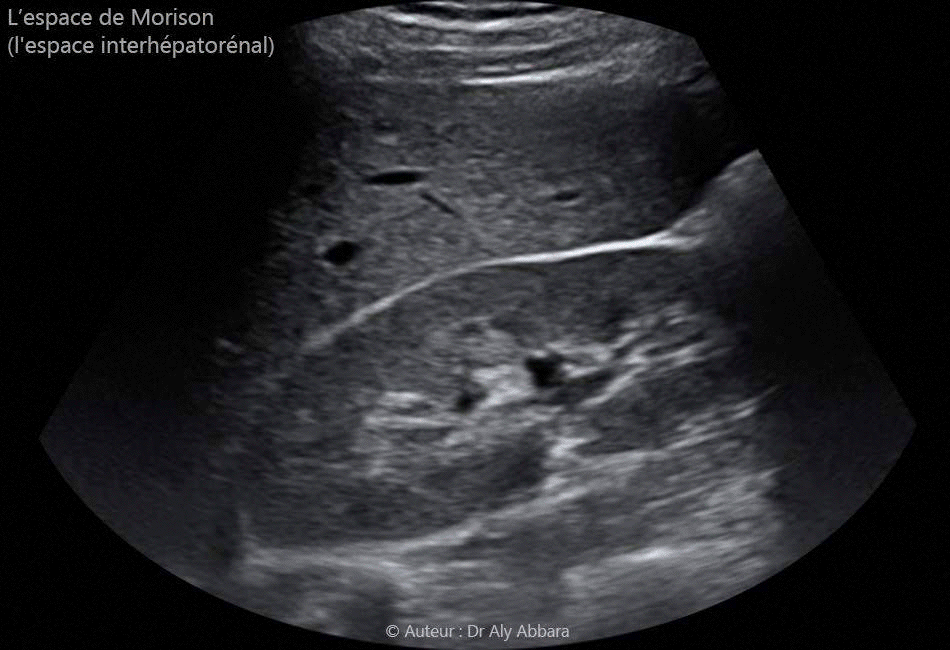

Espace de Morison (espace inter-hépato-rénal) normal

Images échographiques montrant l'aspect échographique normal de l'espace de Morison (ou l'espace interhépatorénal droit ; cet espace est normalement virtuel (aucun épanchement l'occupe comme c'est le sur ces images).

Le fait de constater la présence d'un épanchement liquidien (surtout du sang) dans l'espace de Morison est un signale d'alarme indiquant qu'il existe un hémopéritoine intra-péritonéale important, à prendre en charge très rapidement.

L'exploration de l'espace de Morison est impérative en Gynécologie & Obstétrique devant toute urgence pouvant se compliquer d'une hémorragie intrapéritonéale : grossesse ectopique (extra-utérine) ; rupture d'un kyste ovarien ; une douleur abdominale aigue ; une douleur abdominale post-coïtale ; un traumatisme abdominal ; une rupture utérine ; une complication hémorragique intrapéritonéale post-opératoire (post césarienne, ou post toute chirurgie intra-abdominale par laparotomie, par voie vaginale ou par voie cœlioscopique).